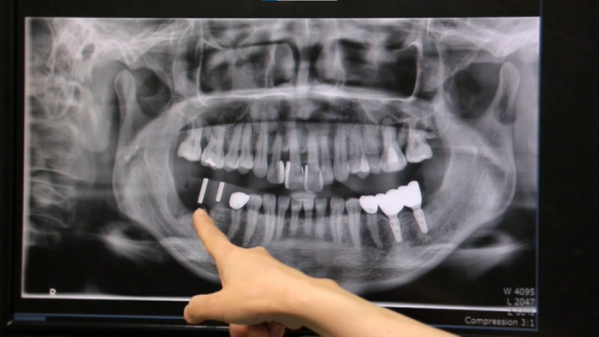

잇몸이 부어올라 병원을 찾은 50대 여성 환자. 1~2달마다 한 번씩 부어오른다는 잇몸. 결국 뼈가 녹아있는 잇몸의 치아를 발치하고 염증 치료에 들어갔다. 단순한 통증이라고 생각했던 일이 어쩌다 발치로까지 이어졌을까?

치주염이 악화된 경우엔 발치와 임플란트 시술 등으로 치료해야 한다. 하지만 고통스럽고 복잡한 과정이 수반된다. 치주염이 발생하기 전에 최대한 예방하는 것이 최고의 방법인 이유다. 예방법의 효과를 알아보기 위해 서로 다른 치아 상태를 가진 지원자들이 전문가의 관리 아래 2주일간의 치아 관리 프로젝트에 돌입한다. 평소 각자의 방법대로 치아를 관리해 오고 있었지만, 잘못된 방법으로 해온 탓에 지원자들의 치아 건강엔 문제가 있는 편이다. 2주일 동안 올바른 양치법과 각자의 구강 상태에 맞는 적절한 치실과 치간 칫솔의 사용을 통해 개선되어 가는 참가자들의 치아 건강을 살펴본다.